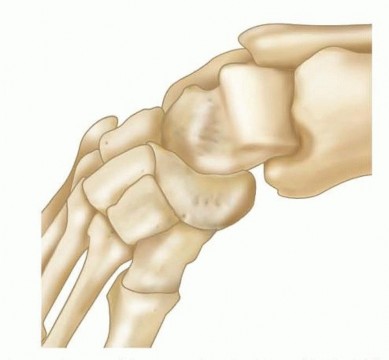

The anterior tibialis muscle is active in two important stages of the gait cycle; it concentrically fires during the initiation of swing phase and keeps the foot dorsiflexed during early swing phase and then it relaxes. The anterior tibialis muscle then fires eccentrically as the foot is lowered to the floor from heel strike to foot flat in stance phase.As a dorsiflexor, the anterior tibialis muscle opposes gravity and the strong gastrocsoleus complex. Importantly, the anterior tibialis muscle may also be a supinator of the forefoot in the face of peroneal longus weakness or medial displacement of the insertion.There are important bony abnormalities associated with residual clubfoot deformity.The subtalar joint may have an absent anterior facet and small, narrow medial and posterior facets, resulting in restricted subtalar motion. In this setting, the calcaneus does not slide fully into valgus with casting such that the navicular remains medially displaced.The navicular itself is wedge-shaped and is medially displaced along with the cuneiforms and metatarsals. 10 With medial displacement of its insertion, the biomechanical advantage favors the action of the anterior tibialismuscle as a strong supinator over its role as a dorsiflexor ( FIG 3). ## PATHOGENESIS The cause of residual clubfoot deformity may be incomplete correction or recurrence of deformity as part of the natural history of the resistant clubfoot.Electromyographic and magnetic resonance imaging (MRI) studies have demonstrated that the peroneal muscle group can be absent, smaller, and relatively weaker, thus increasing the supinator action of the tibialis anterior muscle. 1, 3Medial subluxation of the navicular is considered an important factor influencing both the appearance of the foot and the lateral rotation of the ankle. 9In addition to the bony abnormalities associated with clubfeet, anatomic variations from the customary insertion of the anterior tibialis muscle into adjacent areas of the first metatarsal and medial cuneiform occur in 10% of pathologic specimens.In these variants, the distal anterior tibialis muscle inserts more medially than normal, optimizing the force vector for supination. 8 Illustration 5 for Why Anterior Tibialis Muscle Transfer Fixes Clubfoot --- FIG 3 • Bony abnormalities associated with residual clubfoot deformity. The navicular is wedge-shaped and is medially displaced along with the cuneiforms and metatarsals. Illustration 6 for Why Anterior Tibialis Muscle Transfer Fixes Clubfoot --- * FIG 4 • Hindfoot varus. When untreated, residual deformity may become stiff. When fixed inversion deformity is combined with residual equinus deformity, hindfoot varus occurs. *